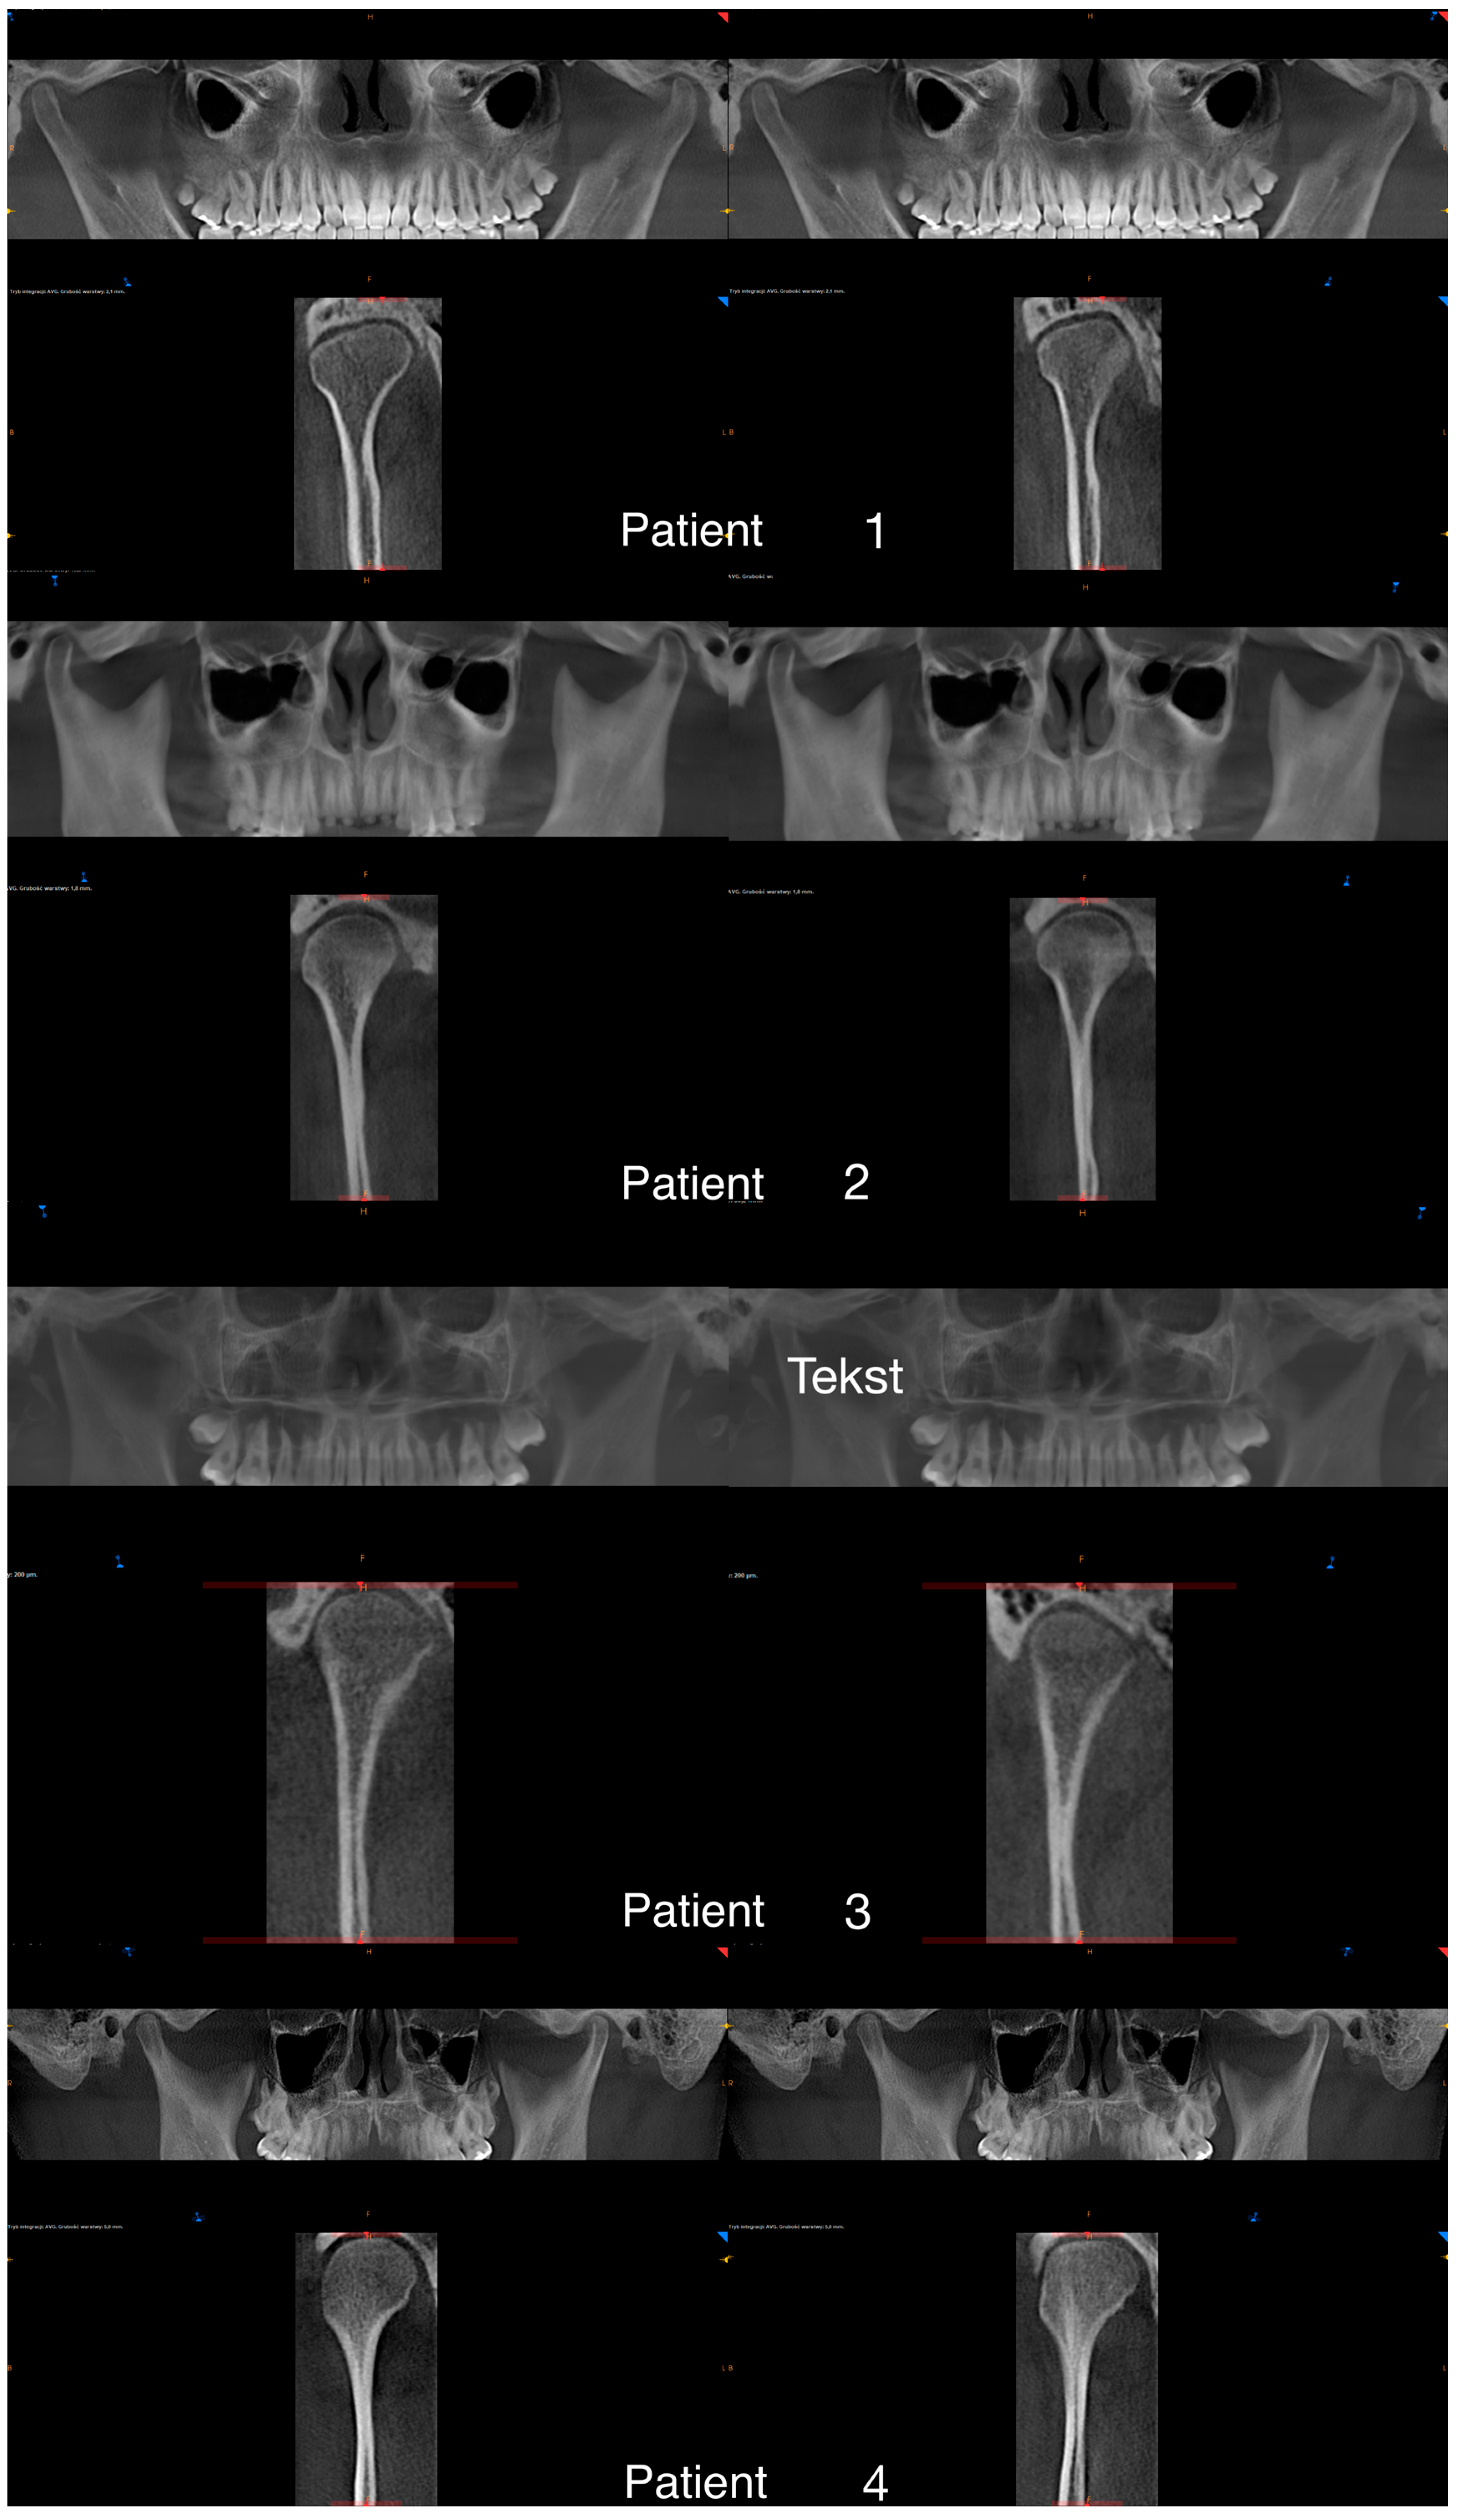

3. The Results of the Treatment